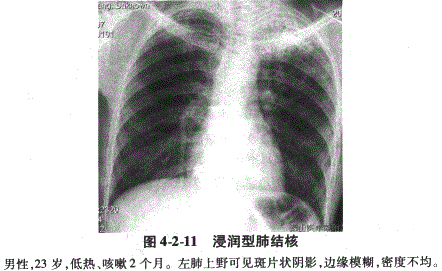

典型浸润型肺结核是继发性肺结核的一种,病灶大多呈斑片状或云絮状,好发于上叶尖后段和下叶背段。病灶可单发或多发,多局限于一侧或两侧肺尖和锁骨下区(肺上野)。病灶边缘模糊,病灶内有空洞形成则表现为病灶内透亮影(图4-2-11)。浸润病灶可与血行播散的肺内粟粒状或结节状病灶并存。